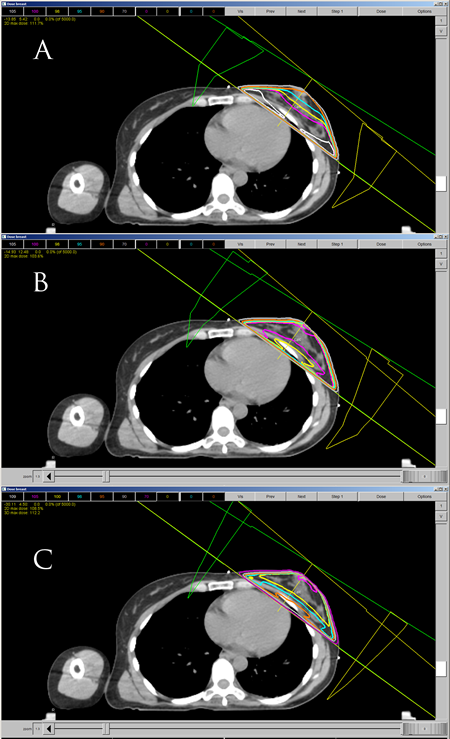

What set of isodose curves best displays homogeneous coverage for left-sided breast cancer?